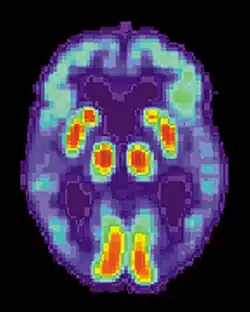

![]() Porównanie budowy mózgu osoby zdrowej (po lewej) i osoby z chorobą Alzheimera (po prawej) | |

Choroba Alzheimera charakteryzuje się utratą neuronów i synaps kory mózgu i pewnych regionów podkorowych. Skutkuje to zanikiem w zajętych obszarach z degeneracją w płatach skroniowych i ciemieniowych, jak też w części płatów czołowych i zakrętach obręczy[37]. Badania z użyciem MRI i PET udokumentowały redukcję rozmiarów specyficznych obszarów mózgu chorych na AD, gdy przechodzili oni z etapu łagodnych zaburzeń poznawczych do choroby Alzheimera, w porównaniu ze zdrowymi ludźmi w podeszłym wieku[71][72].

Jeśli są dostępne, metody neuroobrazowania za pomocą SPECT i PET mogą zostać użyte do potwierdzenia diagnozy choroby Alzheimera w połączeniu z oceną stanu umysłowego[122]. U osoby już wykazującej otępienie SPECT wydaje się mieć przewagę w różnicowaniu choroby Alzheimera i innych możliwych przyczyn nad zwyczajowym postępowaniem z użyciem testów umysłowych i analizą historii choroby[123]. Korzyści te doprowadziły do propozycji nowych kryteriów diagnostycznych[5][104].